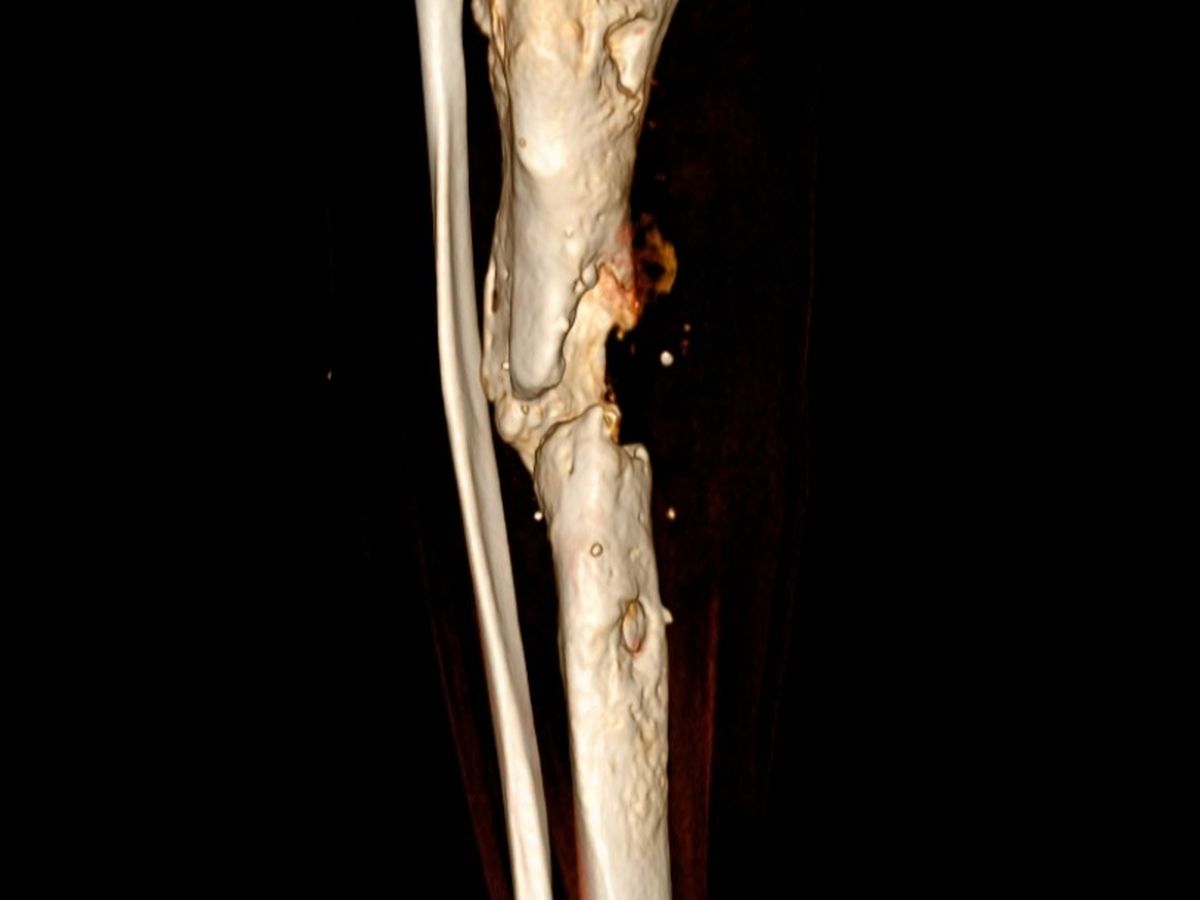

Hace más de un año y medio debido a un accidente practicando cheerleading me rompí la pierna. Todo iba muy bien hasta que comencé con un rechazo de material. He pasado por 3 cirugías para poder volver a caminar pero las cosas se conolicaron... tengo ya una infección en el hueso (osteomielitis) hace poco me dijeron que estaba apunto de perderla por ello (Las imagenes son de mi Xray y mi tomografía). Antes sentía que volaba, y ahora estoy anclado a una cama.